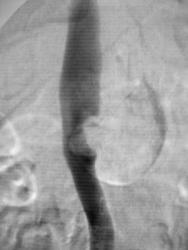

A renal artery aneurysm (RAA) is defined as a dilated segment of renal artery that exceeds twice the diameter of a normal renal artery. Symptomatic RAAs can cause hypertension, pain, hematuria, and renal infarction.

CT scanning accurately demonstrates dilation of the aorta and involvement of major branch vessels proximally and distally. This information helps in determining the appropriate intervention, which may be either surgical or endovascular repair. (See the image below.)